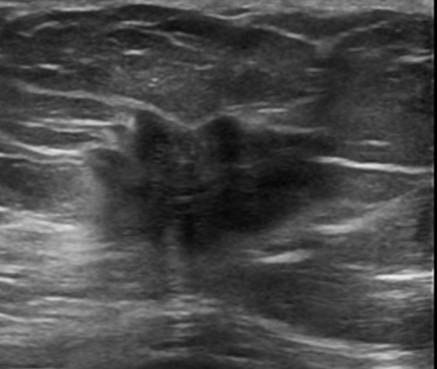

Ung thư vú

» Thông tin: Nữ giới – 72 tuổi.

» Lâm sàng: Khối tuyến vú.